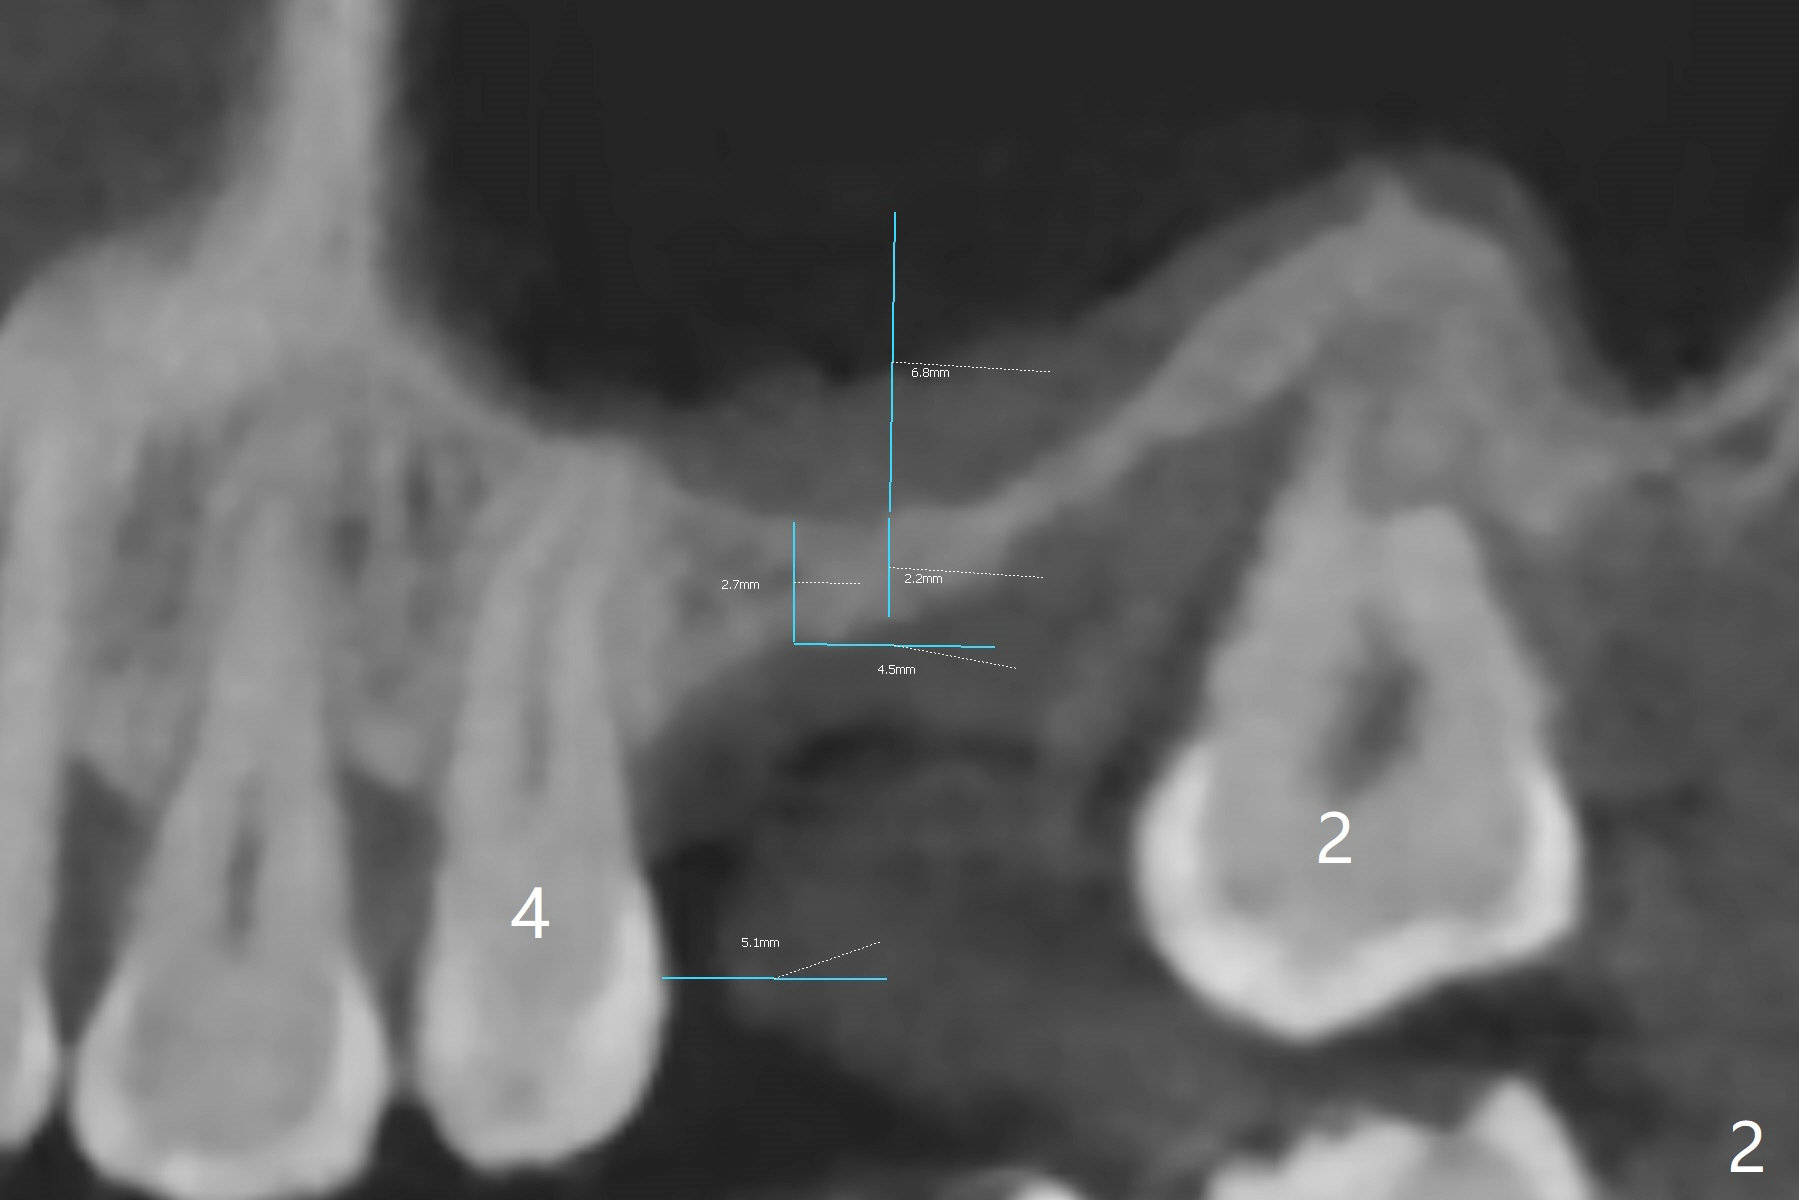

A 42-year-old man is interested in restoring the missing teeth #3 and 9 with implants after that at #14. It appears that the bone density at the ridge of #3 is low (Fig.1 *). Sinus lift may be accomplished directly with Magic Sinus Lifter. If not, use short Magic Drill with 1 and then 2 mm stoppers (Fig.2,3). Since the sinus floor is thicker mesially (Fig.2), establish osteotomy as mesial as possible. Lean Lindamann bur or Magic Drill mesially if needed. Place PRF and Vanilla Graft before insertion of a 4x9 mm dummy implant.